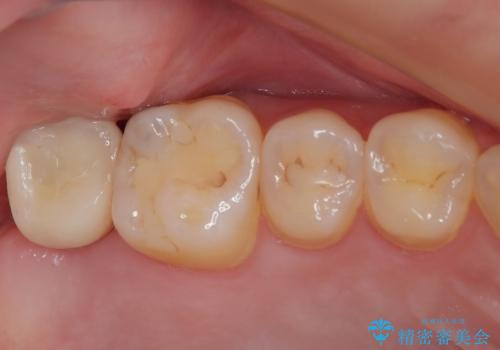

放置したむし歯 抜歯後にインプラントで補綴治療

銀歯をなくしたい 全顎的なむし歯治療